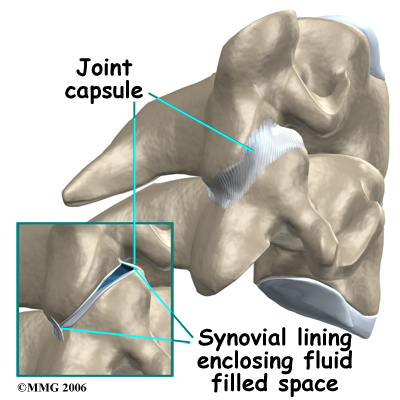

As mentioned above, there are several rheumatological diseases that can affect the spine. One of the most common rheumatological diseases is rheumatoid arthritis (RA). RA primarily attacks the synovial joints and unfortunately a lot of the joints in the body are synovial joints, such as the knee, hip, shoulder, and knuckle joints. Synovial joints are flexible connections that require the two bones can move against one another. The ends of the bones are covered with articular cartilage. Articular cartilage is a white, shiny material that is very slippery and has a limited blood supply. It provides shock absorption and allows the bones to glide easily against one another. The synovial joint is completely enclosed by a joint capsule made up of tough connective tissue on the outside and a thin layer of tissue on the inside called the synovial lining. Inside the joint there is a small amount of fluid called synovial fluid. The synovial fluid brings nutrients to the articular cartilage as it lubricates the joint.